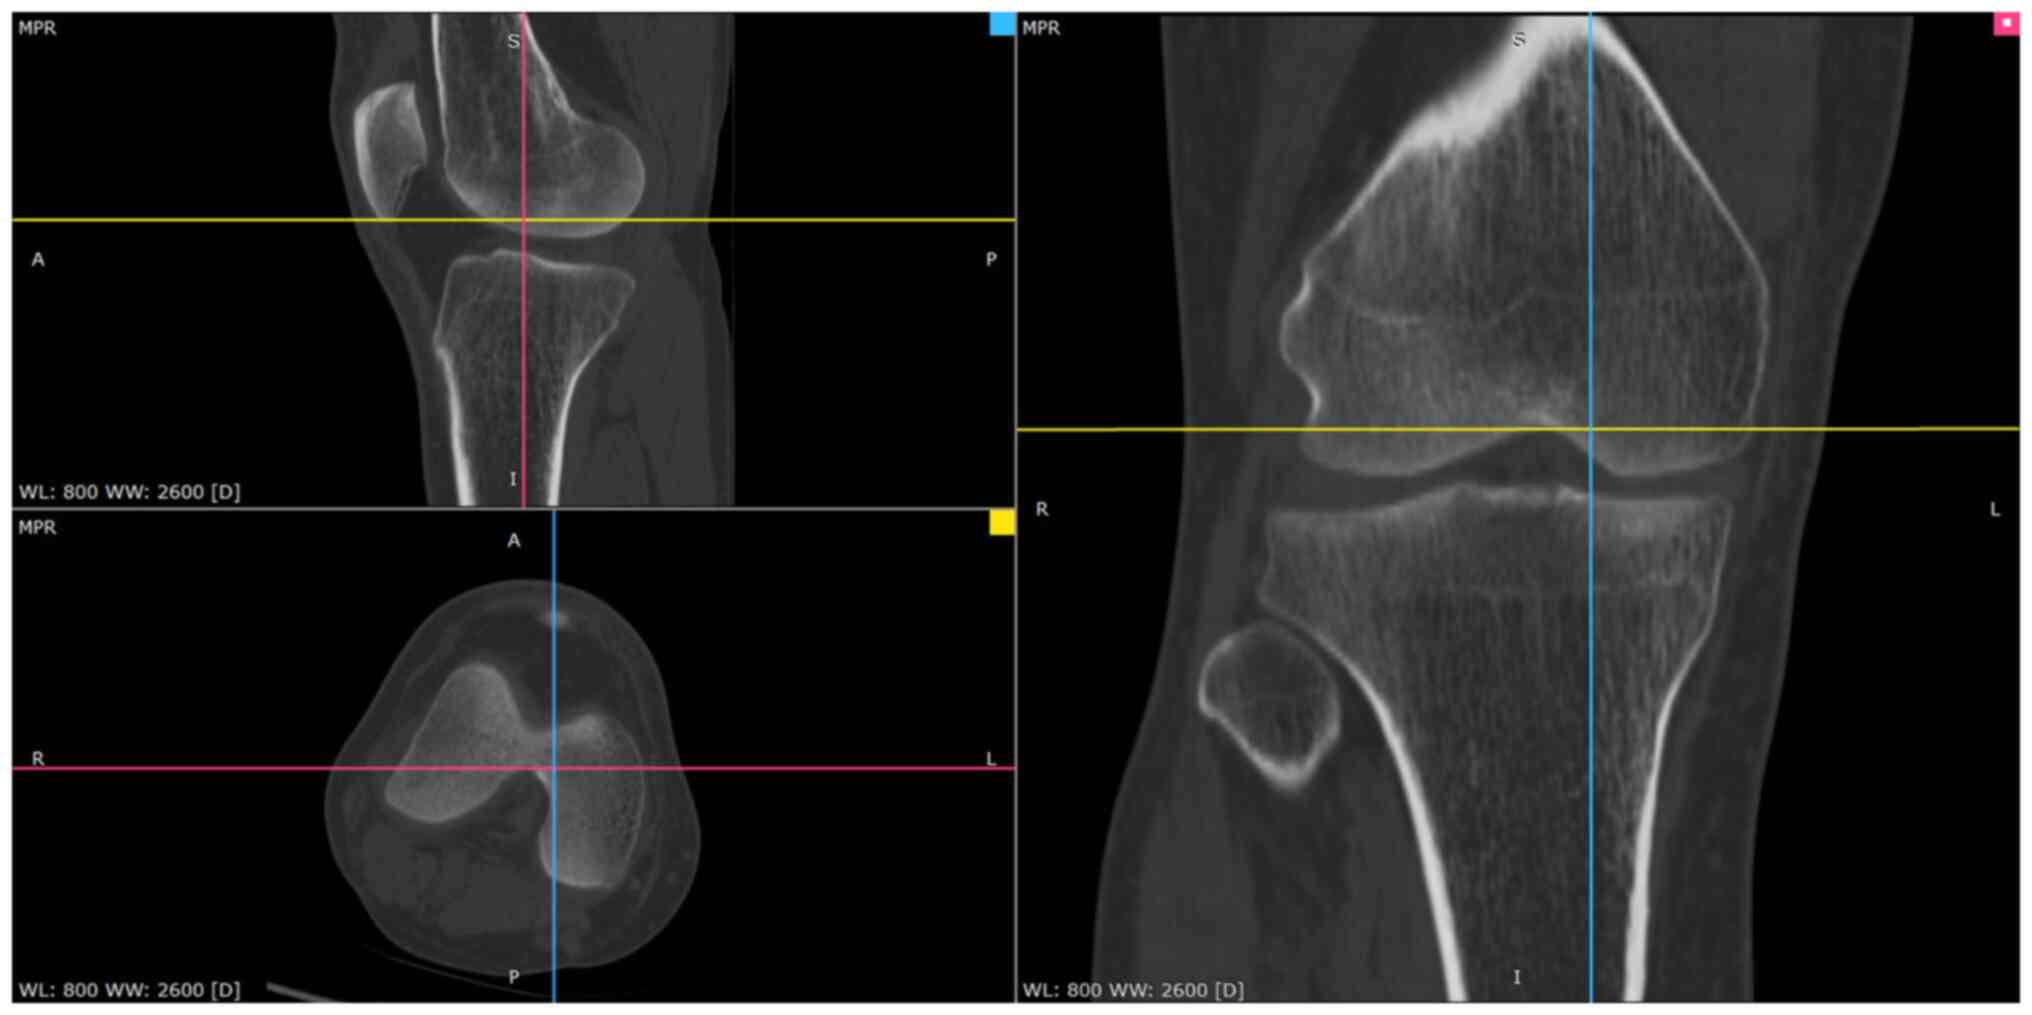

Figure 2

Computed tomography image of the patient. MPR, multiplanar reformation; WL, window level; WW, window width.